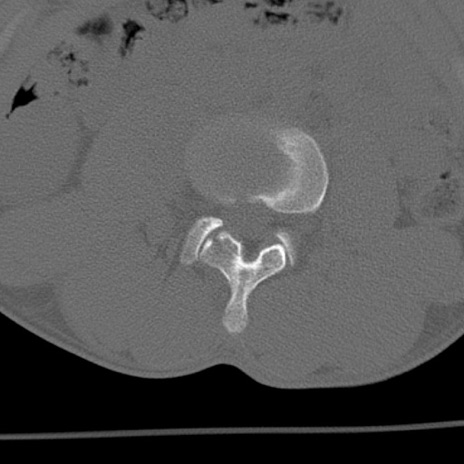

症例3 腰椎CT(横断像)

腰椎CT